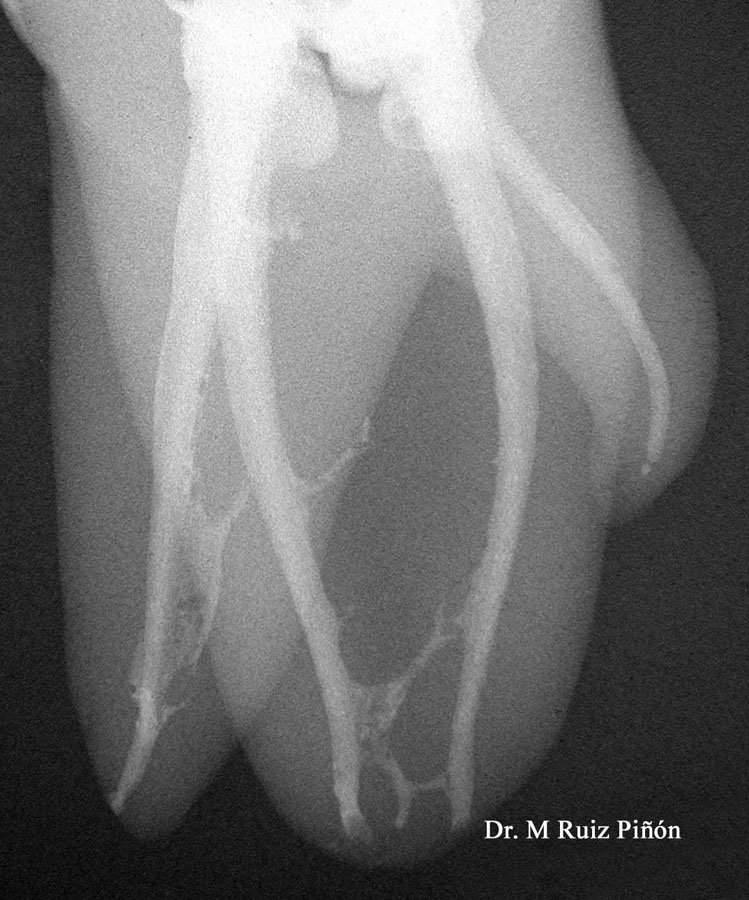

Para poder estudiar la compleja anatomía interna de los dientes nos ayudamos de la radiología convencional y además del CBCT para poder trabadjar con seguridad y diagnosticar correctamente cada caso.

Normalmente los conductos radiculares por donde se dispone la pulpa se ramifican creando en su conjunto lo que denomina un sistema de conductos (1, 2); además no son rectos, y en ocasiones presentan grandes curvaturas que son muy difíciles de limpiar y sellar tridimensionalmente(3-4). Las calcificaciones, i